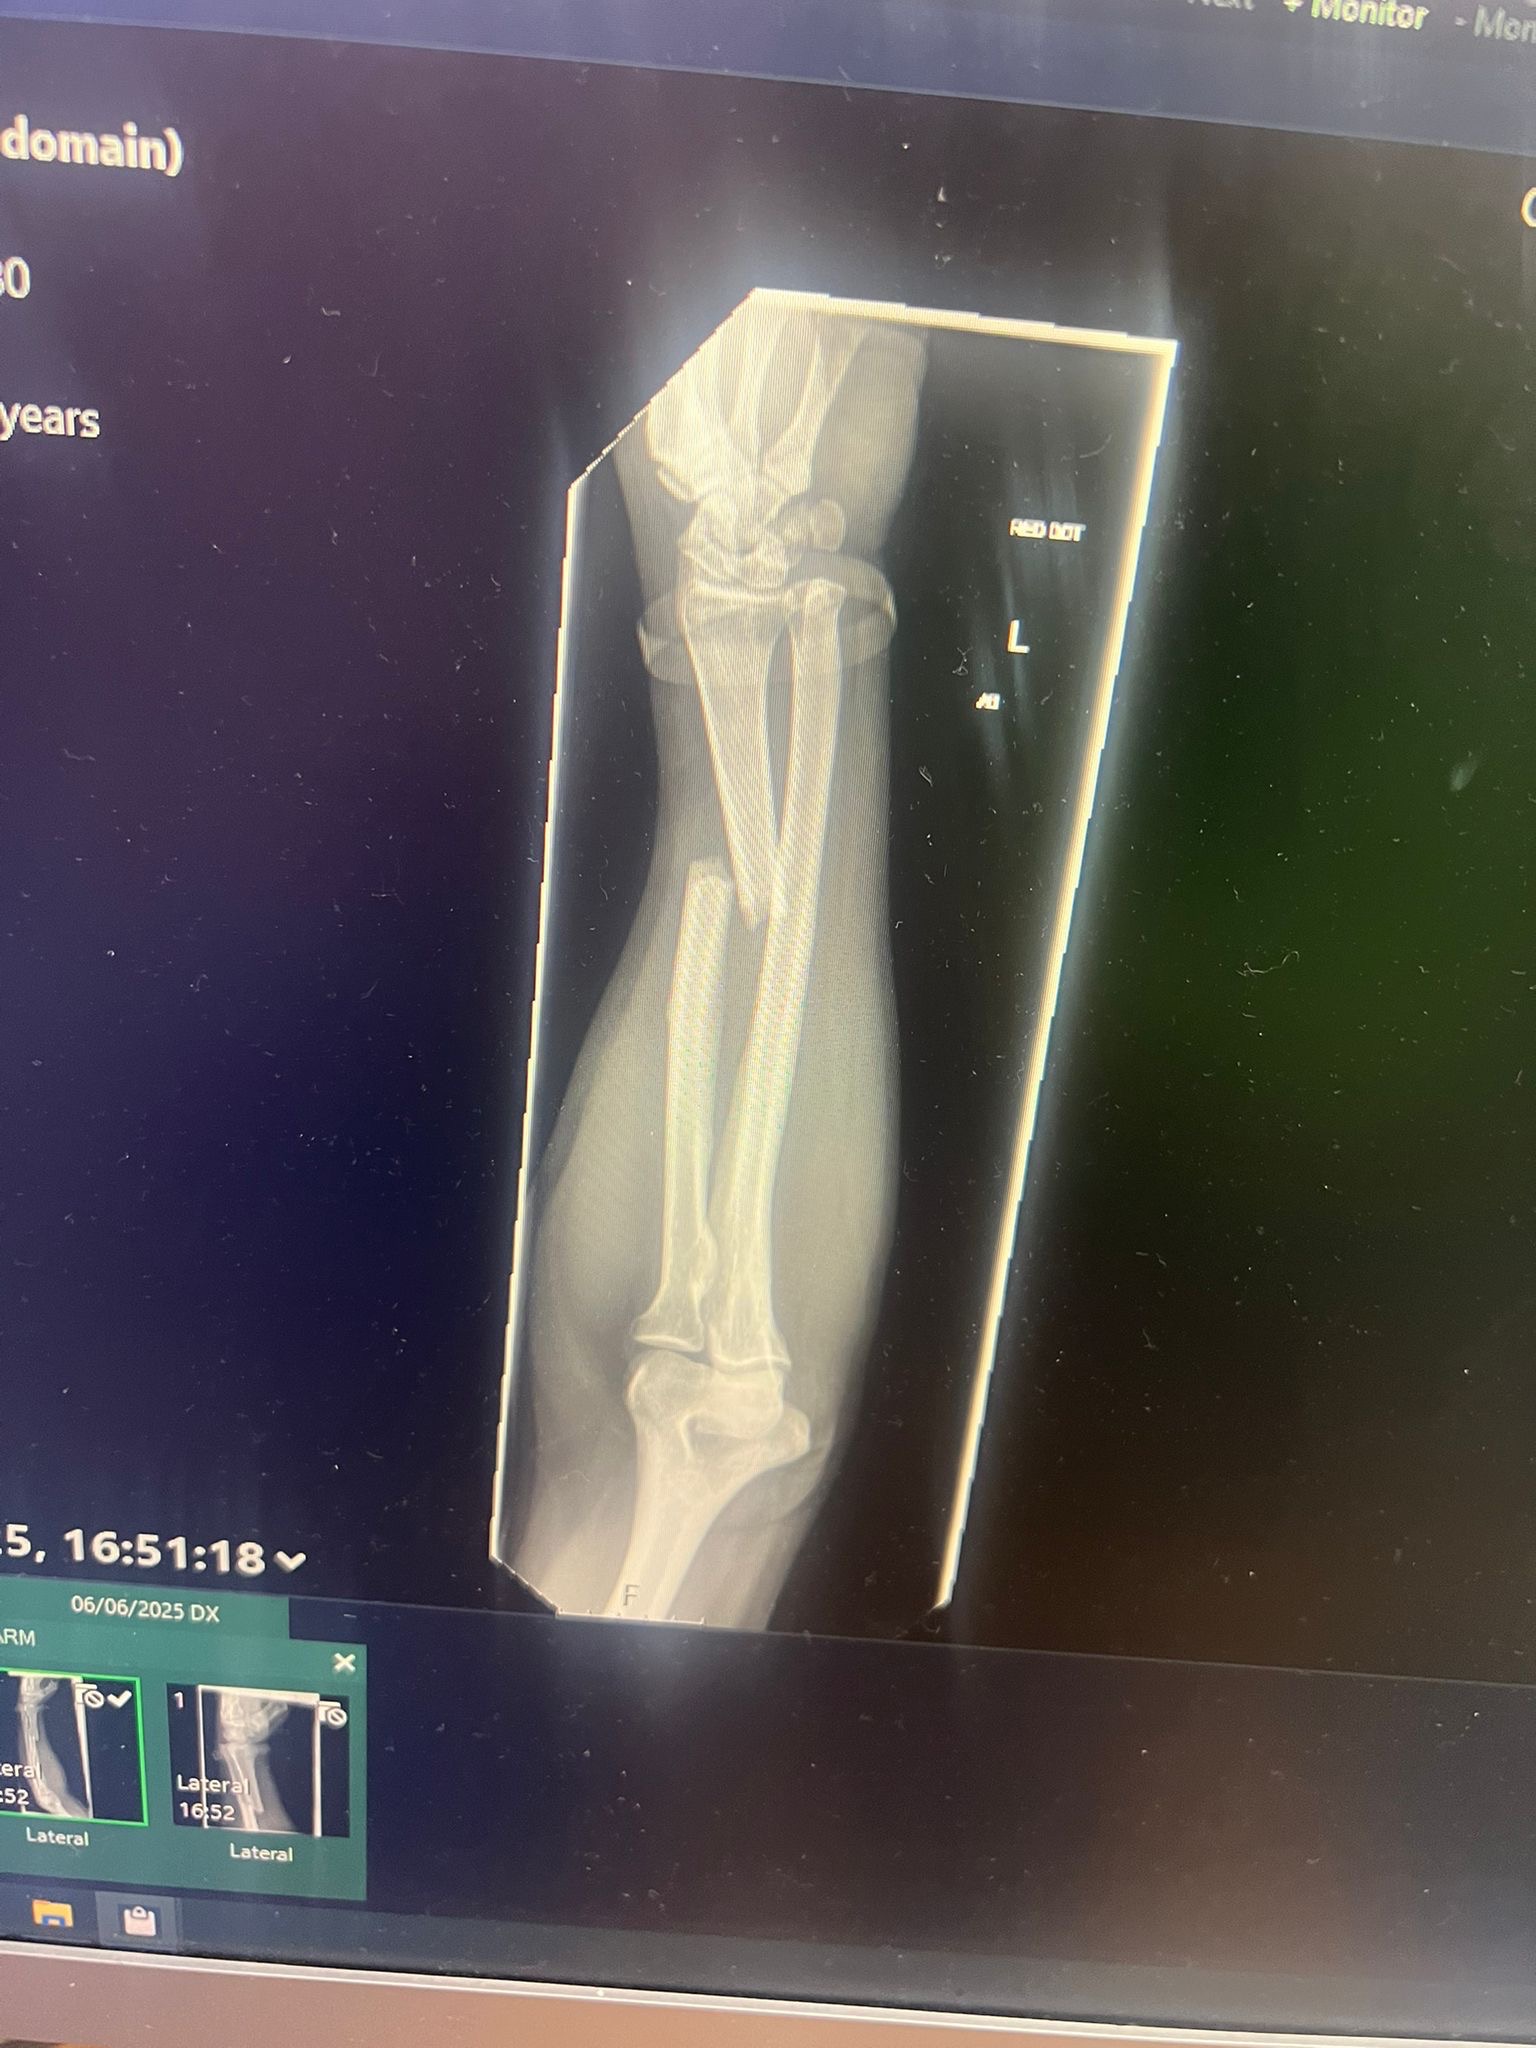

Mark suffered a displaced fracture of the radius bone in his left arm, requiring open reduction and internal fixation—in simpler terms, a small titanium upgrade. Unfortunately, this is beyond even the skills of our trusty Slick to fix this time.